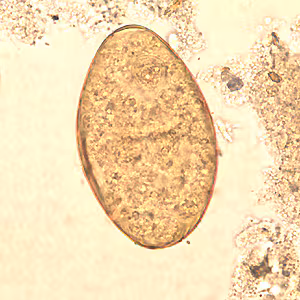

Fasciolopsis buski eggs.

Microscopic identification of eggs, or more rarely of the adult flukes, in the stool or vomitus is the basis of specific diagnosis. The eggs are indistinguishable from those of Fasciola hepatica.